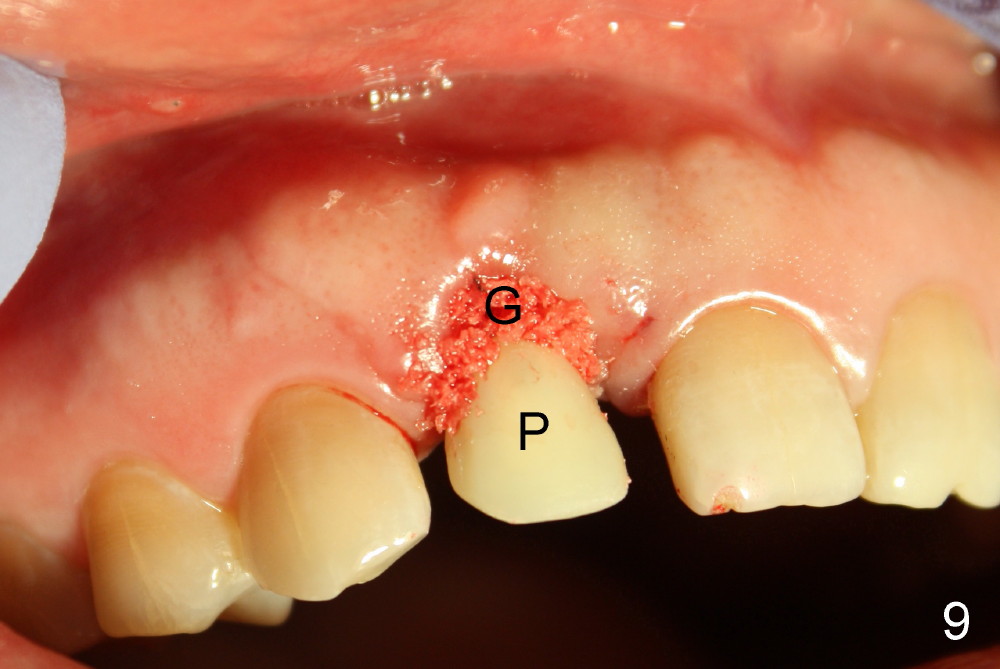

Malpositioned implant in the anterior region is cosmetically unacceptable. Immediate provisional allows us to note the issue immediately. The crown looks too long. Secondly, the provisional is easily dislodged, since the buccal aspect of the angled abutment is over trimmed (Fig.1). The implant (3.8x14 mm), which has been placed 3.5 months, is unexpectedly easily removed by reverse torque (Fig.2). The buccal wall is intact, whereas there seems to be enough bone lingually to place an implant. A small incision is made (Fig.11) so that the gingival tissue can be transferred buccally (Fig.12) and the immediate implant is to be placed palatally (Fig.13 white circle). There is no difficulty forming osteotomy in the palatal wall, followed by inserting 4.5x20 mm tap at the depth of 17 mm (Fig.3,5). But the tap is not palatal enough (Fig.4). By removing more palatal bone, the 4.5x17 implant (Fig.6) appears to be placed palatally enough for restoration (Fig.7; A: abutment; *: buccal gap). The biggest problem is that the palatal flap (Fig.7 arrowheads) cannot be pushed buccally; instead remains palatally. This leads to buccal tissue deficiency (Fig.8). Connective tissue graft is offered, but declined. The patient insists that she has low smile line. Following immediate provisional, mixture of allograft and synthetic graft is placed in the buccal gap (Fig.9). The overbuilt graft is held in place by perio dressing.